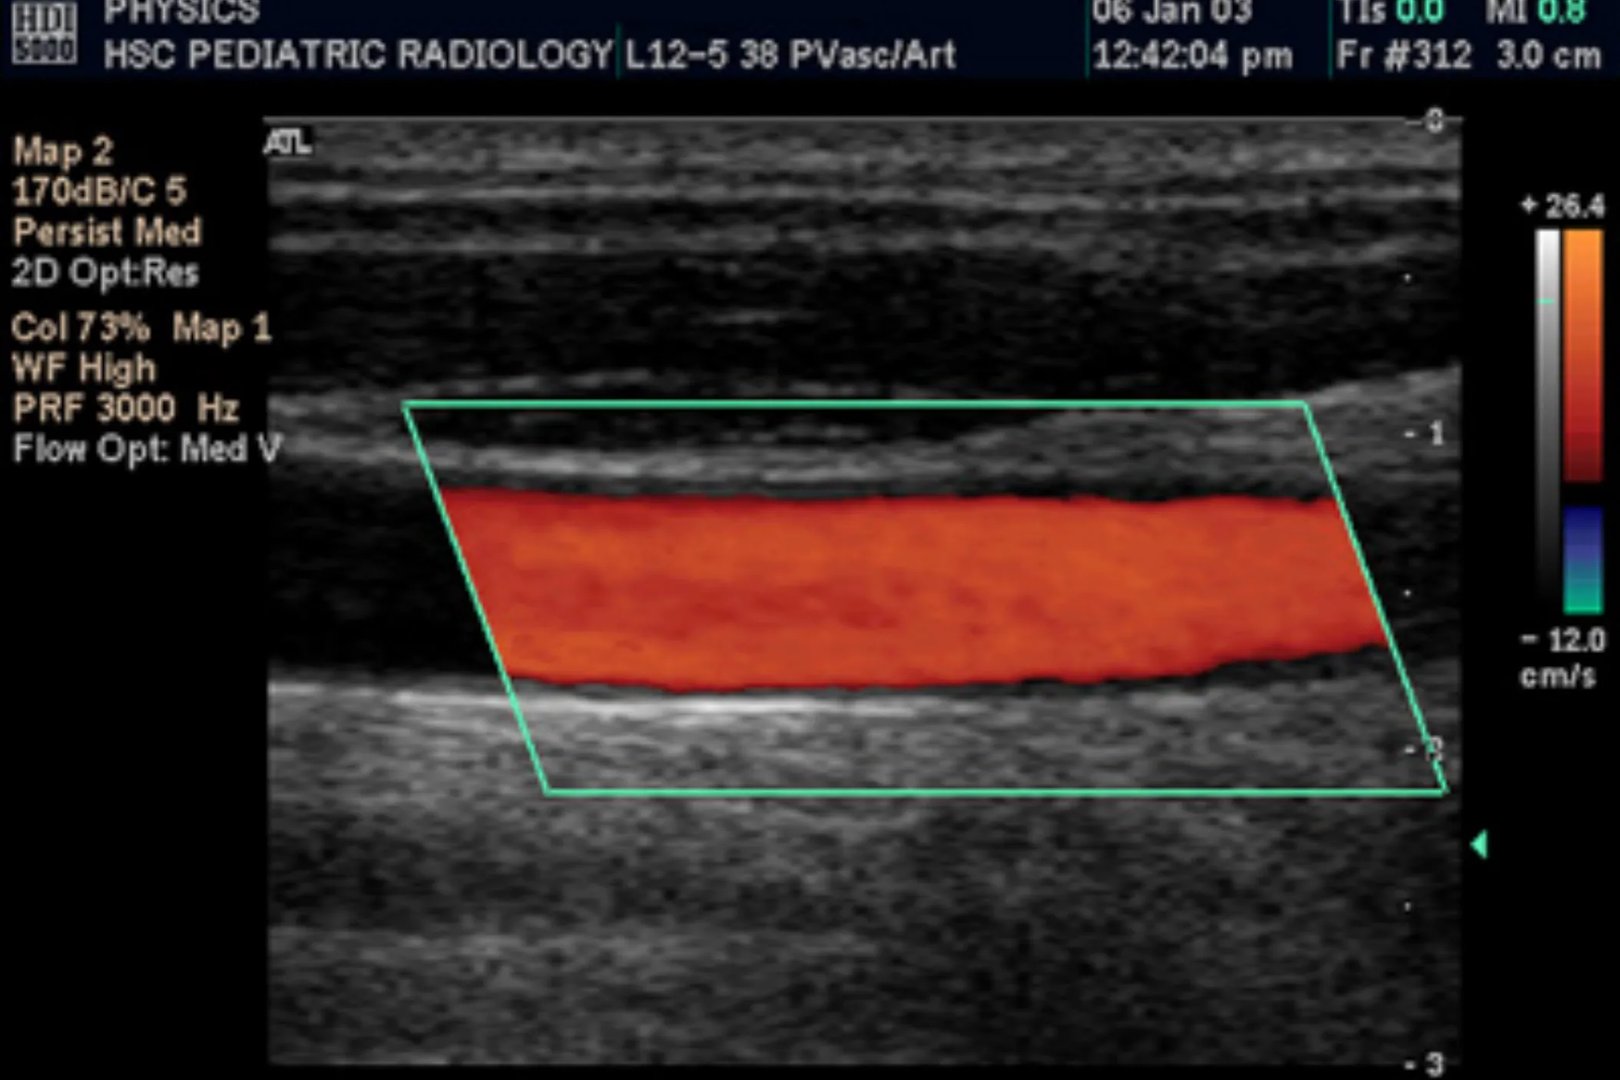

的有关信息介绍如下:彩超是彩色多普勒超声的简称,可对血管、腹腔脏器、心脏、子宫及附件、小器官、前列腺及精囊等全身性脏器进行检查。